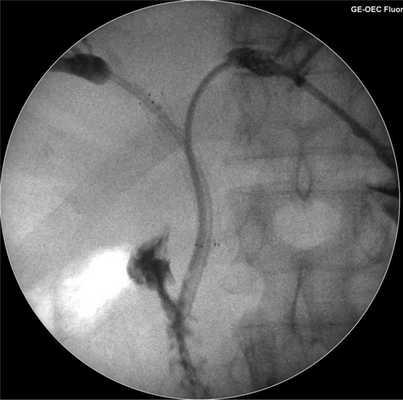

В-третьих, следует остановиться на целесообразности эндобилиарного стентирования зоны опухолевой обструкции саморасширяющимися стентами c паллиативной целью. Методом выбора считается использование саморасширяющихся непокрытых стентов. При всей привлекательности этого метода с точки зрения качества жизни пациентов следует учитывать продолжительность остающейся жизни таких пациентов, которая довольно вариабельна и может превышать 6 мес; этого окажется достаточно для блокады стента с рецидивом синдрома механической желтухи, но в гораздо худших функциональных условиях, чем при первичном стентировании. Кроме того, имплантация эндобилиарного стента существенно затрудняет или полностью исключает проведение внутрипросветного воздействия на опухоль. В такой ситуации, на наш взгляд, целесообразно использовать «гибридное» эндобилиарное стентирование в супрапапиллярном варианте - сохраняя наружновнутренний дренаж в просвете эндобилиарного стента. Такой вариант стентирования, кроме всего прочего, позволяет контролировать и корригировать проходимость стента.

Использование покрытых или частично покрытых стентов при нерезектабельной опухоли Клацкина не рекомендуется из-за риска сформировать синдром недренируемой доли или сегмента. Такой вариант внутреннего дренирования, однако, вполне допустим и оправдан у пациентов с резектабельной опухолью при односторонней установке стента в долевой проток со стороны предполагаемой к сохранению паренхимы печени. Вместе с тем, если после установки покрытого стента в ходе последующей операции выяснится нерезектабельность опухоли ворот печени, желчные протоки контралатеральной доли будут дренированы лишь наружно, в то время как при первичном использовании непокрытого стента можно выполнить контралатеральное Y-образное или гибридное стентирование (рис. 4).

Рис. 4. Антеградная холангиограмма пациента с опухолью Клацкина тип III по Bismuth. Гибридное наружновнутреннее дренирование желчных протоков правой половины печени на базе саморасширяющегося непокрытого стента. Наружновнутреннее дренирование желчного дерева левой половины печени через ячейку непокрытого стента.